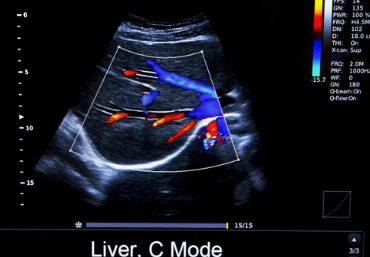

간 기능 검사는 혈액 검사를 통해 간의 건강 상태를 확인하는 검사입니다. 간은 다양한 기능을 수행하기 때문에 여러 가지 항목을 검사하여 종합적으로 평가합니다. 간 기능 검사를 통해 간염, 간경변, 지방간 등 다양한 간 질환을 조기에 발견하고 치료할 수 있습니다.